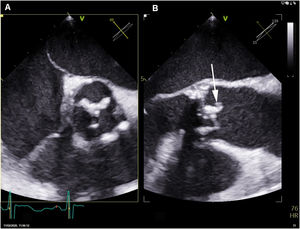

La ecocardiografía transesofágica demostró la presencia de velos engrosados en la bioprótesis, sin imágenes indicativas de vegetaciones ni afectación anular. Se realizó PET/TC con flúor-18-fluorodesoxiglucosa, observándose un intenso depósito hipermetabólico sobre la prótesis valvular aórtica, así como captación difusa a nivel esplénico (fig. 1).

Inicialmente se planteó tratar el cuadro solamente con tratamiento médico. Doce días después de iniciar el tratamiento antibiótico se repitió el ecocardiograma transesofágico, que demostró la presencia de una imagen móvil en el borde libre del velo no coronariano de la prótesis, por lo que se indicó tratamiento quirúrgico consistente en la resección de la prótesis infectada e implante de una nueva (fig. 2).